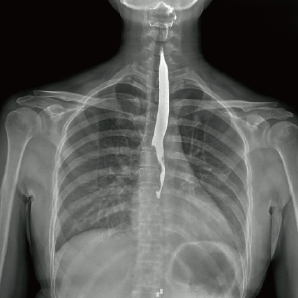

l 数字化透视

适用于身体各部位透视功能(如胸部、腹部等)

l 数字化造影

可以进行对比研究,例如食管造影、静脉肾盂造影和输卵管造影